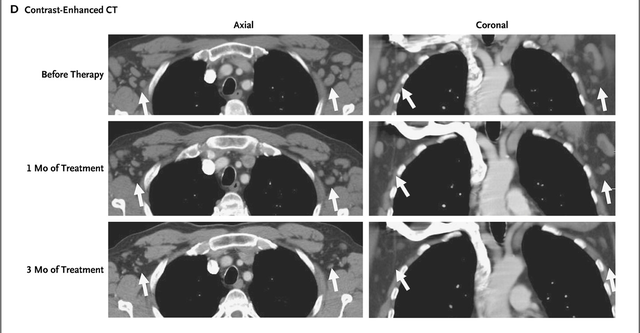

CAR-T细胞输注第28天,淋巴结肿大不再可触及,第23天,骨髓中已经没有慢性淋巴细胞白血病的迹象。输注后第31天的CT扫描显示淋巴结肿大消退。CAR-T细胞输注3个月后,CT扫描显示持续缓解。

图片源于新英格兰医学杂志